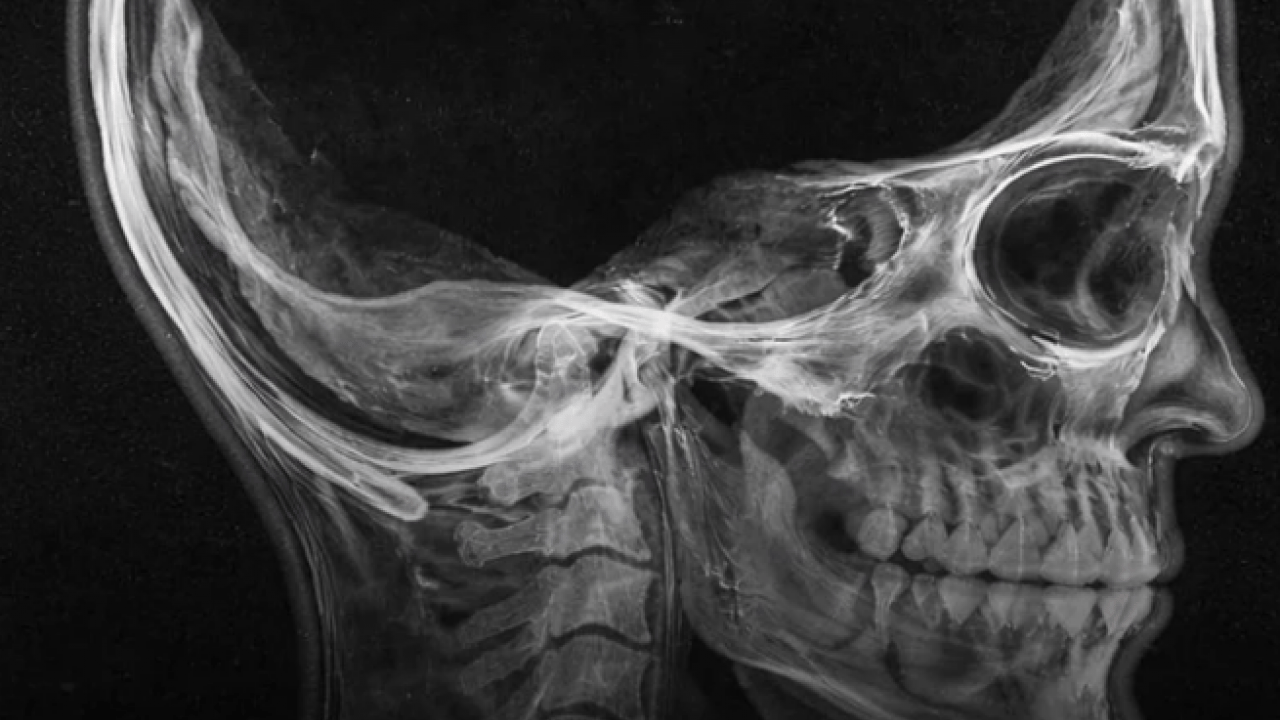

Uzmanlara göre sosyal medyada sıkça paylaşılan “beynin yüzde 90’ı yok” iddiası gerçeği tam olarak yansıtmıyor. Vakada, beynin tamamen kaybolması değil, hidrosefali adı verilen bir rahatsızlık nedeniyle yıllar içinde küçülmesi ve kafatasının kenarlarına doğru itilmesi söz konusu.

Bu durum, beyin dokusunun ince bir tabaka halinde kalmasına rağmen temel işlevlerin devam edebilmesini sağladı.

Araştırmalara konu olan kişinin evli olduğu, çocuk sahibi olduğu ve düzenli bir işte çalıştığı belirtildi. IQ seviyesinin ortalamanın altında olduğu ancak günlük yaşamını sürdürebilecek düzeyde olduğu ifade edildi.